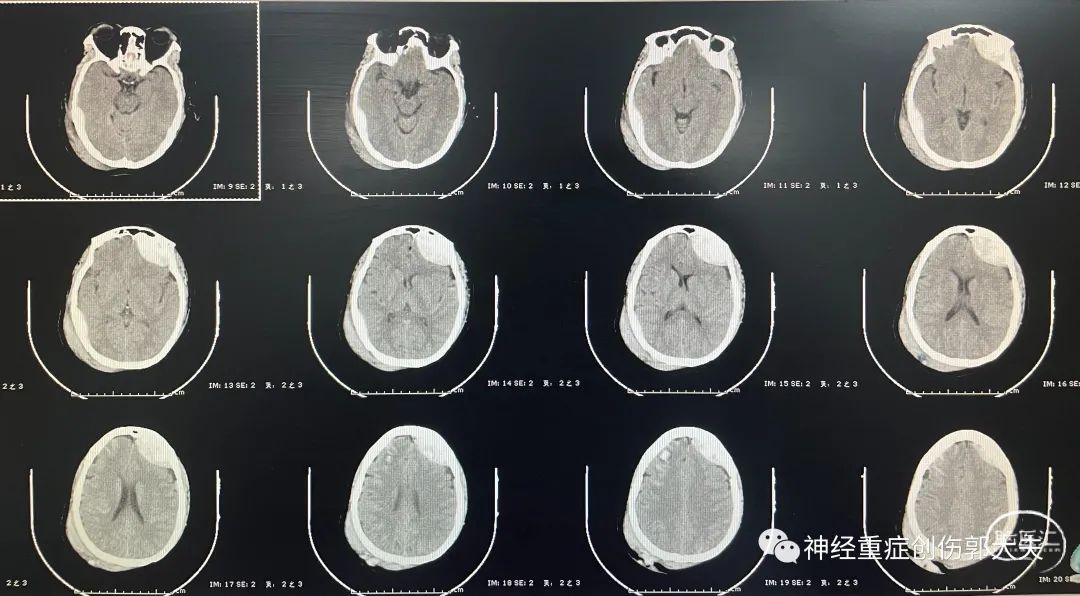

患者男性,52岁,主因“意识障碍8小时”入院,神志中昏迷,GCS5分,既往高血压病史,头颅CT显示左侧基底节区脑出血破入脑室。

急诊行右侧脑室外引流+左额颞顶开颅血肿清除+去骨瓣减压术,术后复查移动CT显示引流管位于侧脑室内,血肿清除满意。